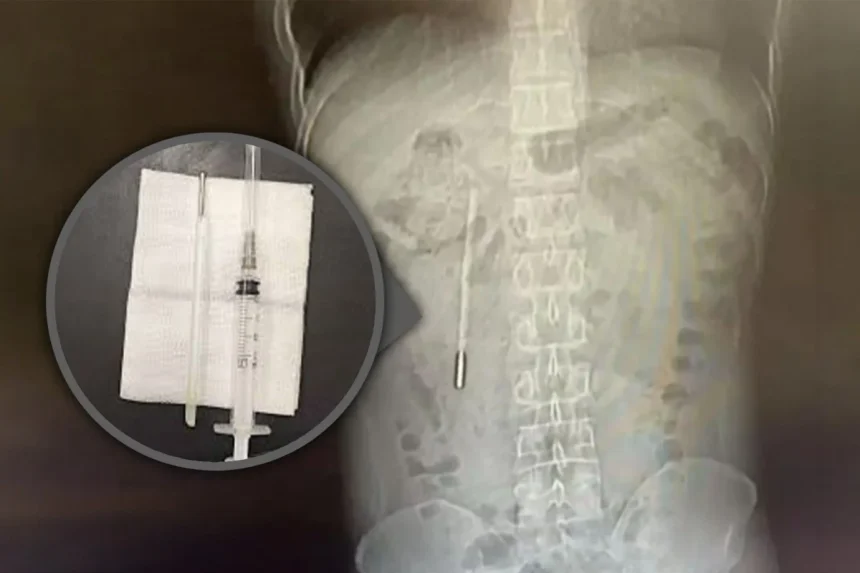

Un bărbat chinez în vârstă de 32 de ani, cunoscut sub numele de Wang, a ajuns la spital din cauza durerilor de stomac, iar medicii au descoperit un termometru cu mercur în stomacul său, pe care îl înghițise cu 20 de ani în urmă. Incidentul uluitor a avut loc în Wenzhou, provincia Zhejiang, sud-estul Chinei. Acesta a dezvăluit că a înghițit accidental termometrul la vârsta de 12 ani, dar nu a avut curajul să le spună părinților săi, iar incidentul a fost uitat de-a lungul timpului.

Chirurgii au reușit să îndepărteze termometrul într-o intervenție delicată care a durat 20 de minute. Termometrul fusese reținut în apropierea canalelor biliare, prezentând un risc semnificativ de deteriorare a peretelui intestinal. În ciuda pericolului, operația s-a încheiat cu succes, iar termometrul a fost extras intact, deși marcajele de măsurare se estompaseră.